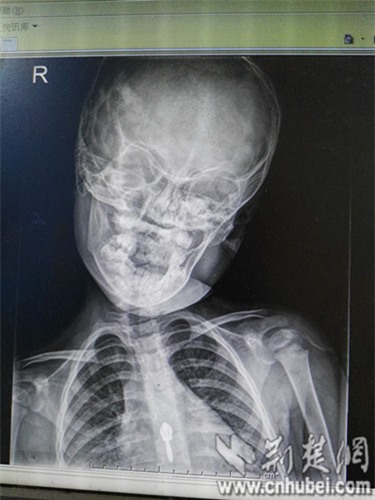

Trước đó, vào tối ngày 11/6/2016, bé gái Phương Phương (3 tuổi) tự nhiên bị sốt cao 38,5 ℃. Sang ngày thứ hai thì bố mẹ thấy em có hiện tượng bị vẹo cổ sang bên trái và cứ thế giữ yên không quay được.

Tình hình có vẻ trầm trọng hơn khi bé bắt đầu quấy khóc, bố mẹ bé đã phải đưa đến bệnh viện Phổ Nhân (Trung Quốc) để khám nghiệm.

Sau khi bác sĩ nhi khoa thăm khám và chẩn đoán là viêm amiđan mủ cấp tính, do cổ của bé có hiện tượng bị hạn chế vận động.

Theo bác sĩ Hồ Tiểu Quân, giám đốc bệnh viện Phổ Nhân, người trực tiếp xem xét bệnh tình của Phương Phương cho biết, bé còn rơi vào hiện tượng căng cơ bắp vùng cổ, xuất hiện đau rõ ràng.

Đây là hiện tượng thoái hóa đốt sống cổ, tổn thương nặng vùng cơ trên phần cổ, cần phải lập tức điều trị phục hồi chức năng, trị liệu nhanh để hồi phục công năng hoạt động của cổ.